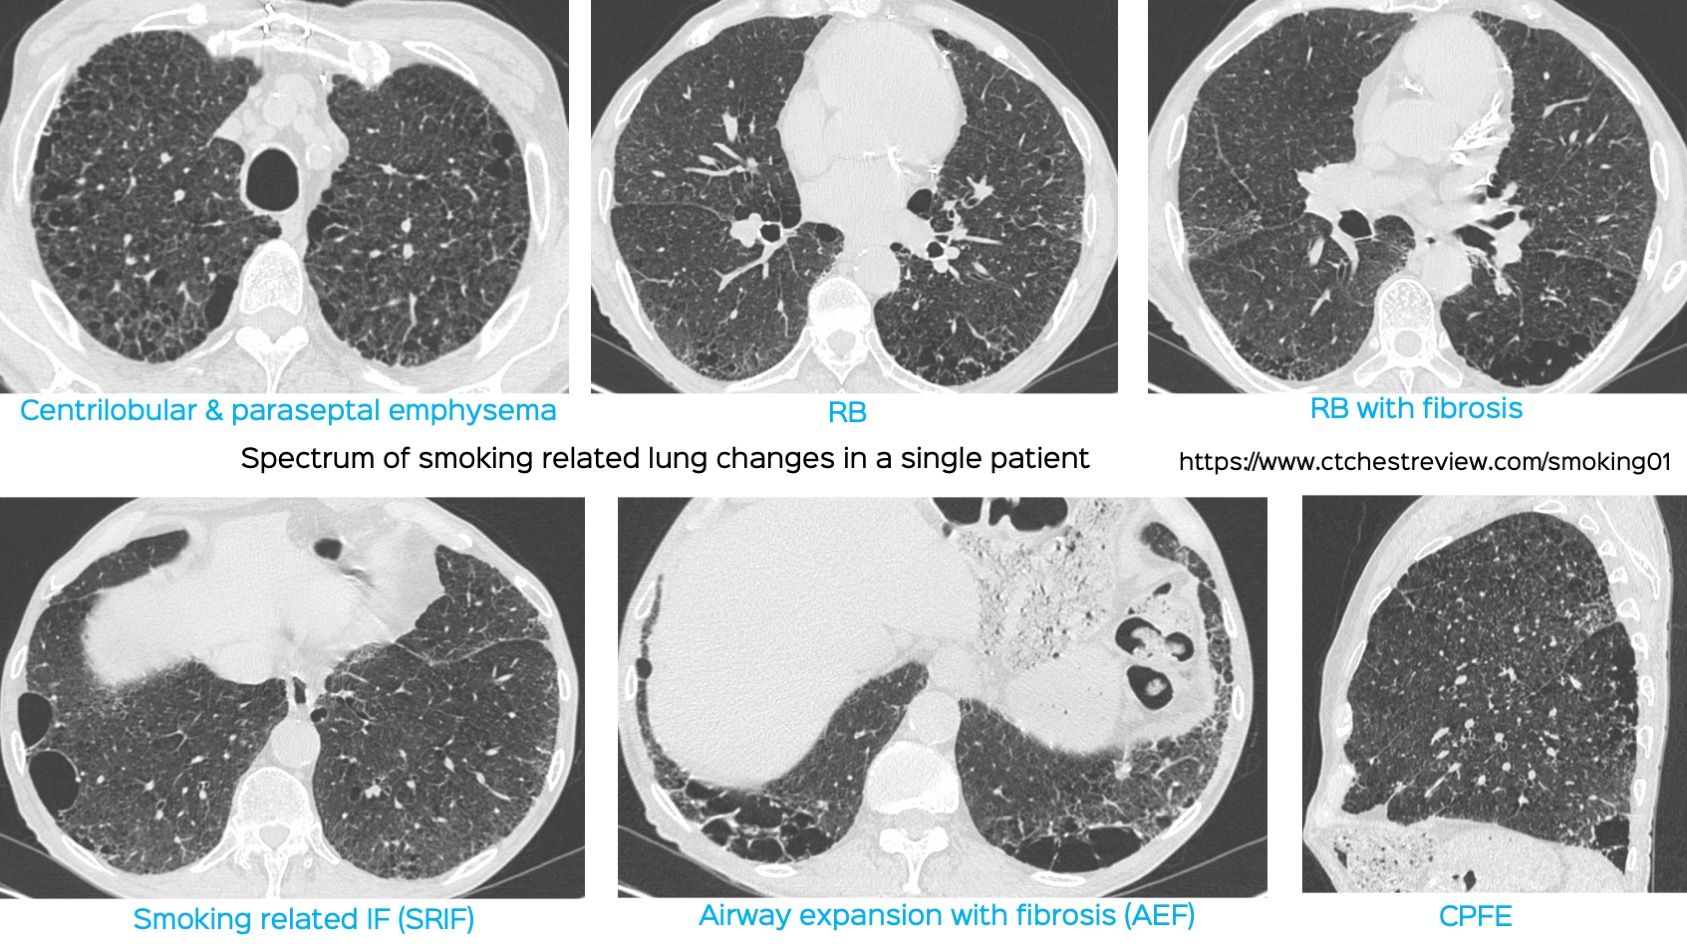

The official research statement on combined pulmonary fibrosis and emphysema (CPFE) was published last week. It has definitions to help us diagnose CPFE from a research perspective as well as clinically.

The video explains the salient features of the statement using a 69-years old 50-pack years smoker as an example.